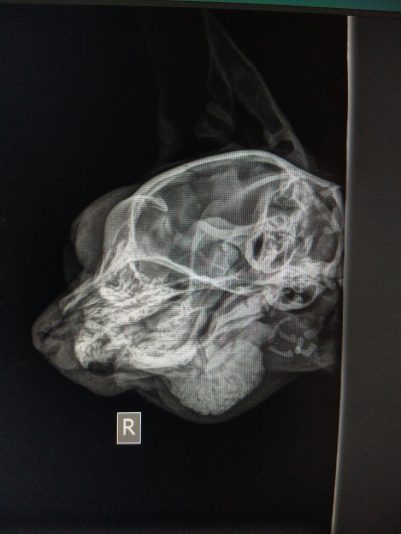

Signalement: Kattin intact van 7m, Europese Korthaar

Anamnese: Enkele weken geleden reeds klachten van manken op achterpoot en gezwollen tarsus. Was de kleinste van het nest en groeide moeilijk. Sinds verhuis erg stil en zit veel minder leven in. Eten, drinken, urineren en defeceren nog normaal.

Klinisch onderzoek: rustig maar alert. HF…